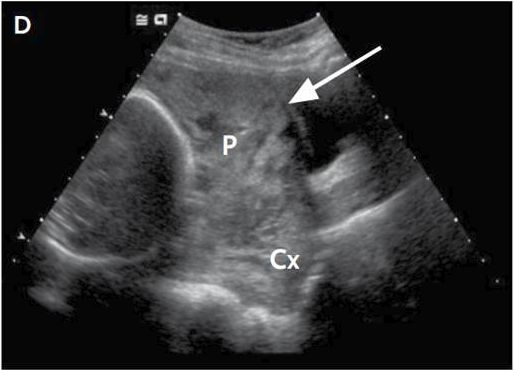

27w超声显示

△

P指不规则低回声区,为胎盘组织;Cx指宫颈;箭头指子宫肌层。

27周超声显示前置胎盘并胎盘粘连明确,故未行MRI。